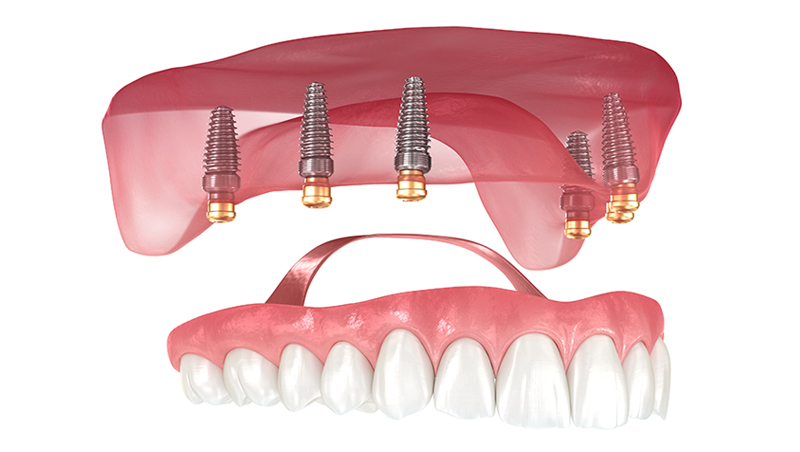

インプラントで固定する入れ歯「インプラントオーバーデンチャー」

インプラントオーバーデンチャーとは、顎の骨に埋入したインプラントを支えとして、入れ歯を安定させる治療法です。通常の総入れ歯は歯肉の粘膜のみで支えるため、ズレやすく、咬む力が十分に伝わりにくいという課題があります。

一方、インプラントオーバーデンチャーでは、インプラントが入れ歯の安定源となることで、咀嚼時の動揺を抑え、しっかりと咬める状態を目指すことが可能です。

また、固定式のフルインプラント治療と比較すると、埋入本数が少なく、外科的負担や費用面を抑えやすい点も特長です。入れ歯は取り外しが可能なため清掃性にも優れており、日常のメインテナンスを重視したい方にも適した治療法です。

2All-on-4(オールオンフォー)

- 4本程度のインプラントで歯列全体を支える固定式補綴

- 短期間で治療が可能な場合もありま

- 固定式なので使用感がより自然に近い